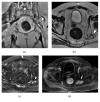

Magnetic resonance neurography is a high-resolution imaging technique that allows evaluating different neurological pathologies in correlation to clinical and the electrophysiological data. The aim of this article is to present a review on the anatomy of the lumbosacral plexus nerves, along with imaging protocols, interpretation pitfalls, and most common pathologies that should be recognized by the radiologist: traumatic, iatrogenic, entrapment, tumoral, infectious, and inflammatory conditions. An extensive series of clinical and imaging cases is presented to illustrate key-points throughout the article.